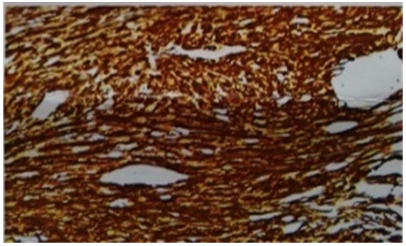

A 53year old lady presented with urgency and frequency for 3months, with two episodes of painless total gross hematuria. She developed acute urinary retention and was catheterized elsewhere and referred to our institute. She had no urological or spine surgeries, no known comorbidities or prior episodes of hematuria. Clinical examination was unremarkable. Ultrasound (US) showed a heterogeneously hypoechoic lesion of 4 x 3 x 4cm in bladder base (Figure 1). Contrast enhanced computed tomogram (CECT) showed a 5 x4 x 4cm well circumscribed hypodense lesion arising from trigone, without hydroureteronephrosis (Figure 2). At cystoscopy, a mucosal bulge measuring around 5 x 5 cm was seen in the right lateral wall extending upto bladder neck and a cecoureterocele was suspected (Figure 3). Transurethral resection (TUR) was done and it showed fragments of tumor tissue composed of spindle cells arranged in sheets and interlacing fascicles, without mitosis or necrosis, suggestive of leiomyoma bladder (Figure 4). Immunohistochemistry showed smooth muscle antigen (SMA) and desmin positivity (Figure 5). Repeat TUR and complete enuceation of the lesion was done. At 6 months of follow up patient is doing well without recurrence or hematuria.

Figure 4 Photomicrograph. Leiomyoma - spindle cells arranged in sheets and interlacing fascicles, without mitosis or necrosis H&E, 40X).

Figure 5 Photomicrograph. Immunohistochemistry showing smooth muscle antigen (SMA) and desmin positivity (40X).